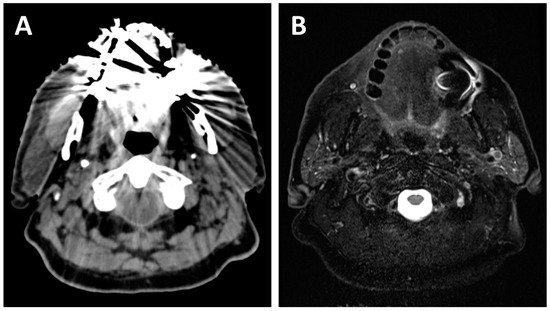

2.1. Local Extension

2.2. Lymph Node Evaluation

4. Assessment of Response

4.1. Before Treatments